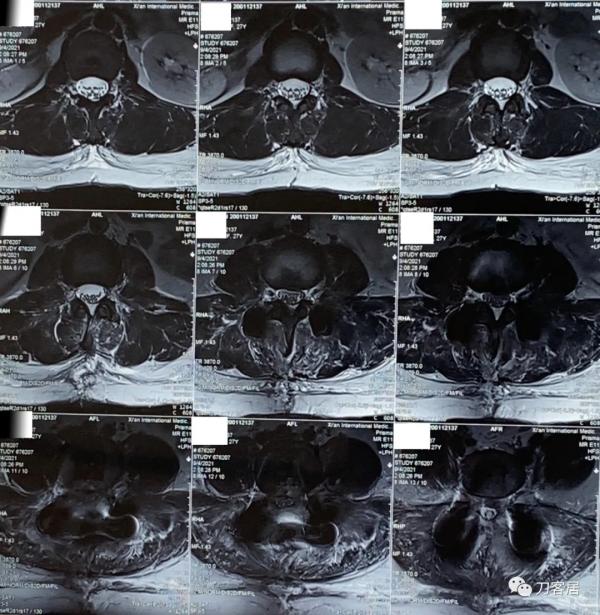

圖16. 20210904術後11天,腰椎MRI橫截面掃描,可見切口內訊號混亂,切口內液性聚集。

圖17. 20210904術後11天,腰椎MRI橫截面掃描,可見切口內訊號混亂,切口內液性聚集。

圖18. 20210920術後27天,腰椎MRI矢狀面,提示切口內訊號混亂,液性聚集。

圖19. 20210920術後27天,腰椎MRI橫截面,提示切口內訊號混亂,液性聚集。